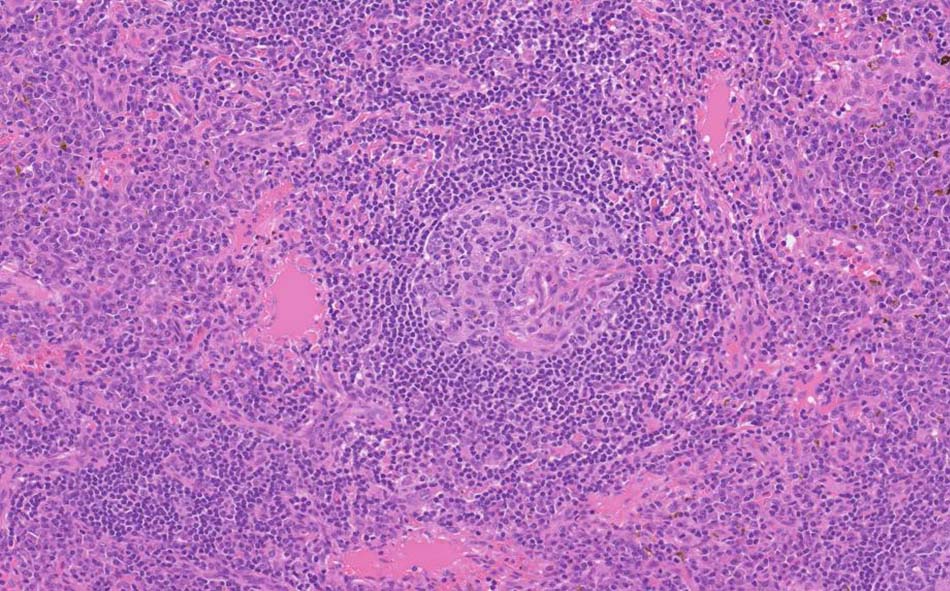

萎縮した胚中心をマントル細胞が取り囲む濾胞構造がびまん性に認められる. 濾胞間には,形質細胞が密に認められる.

萎縮した胚中心には細血管が侵入する特徴的な所見がある. (Lolli-pop germinal center)

免疫染色; リンパ節のplasma cellは多くがIgGが陽性. さらにIgG4陽性plasma cellsが多数をしめる.